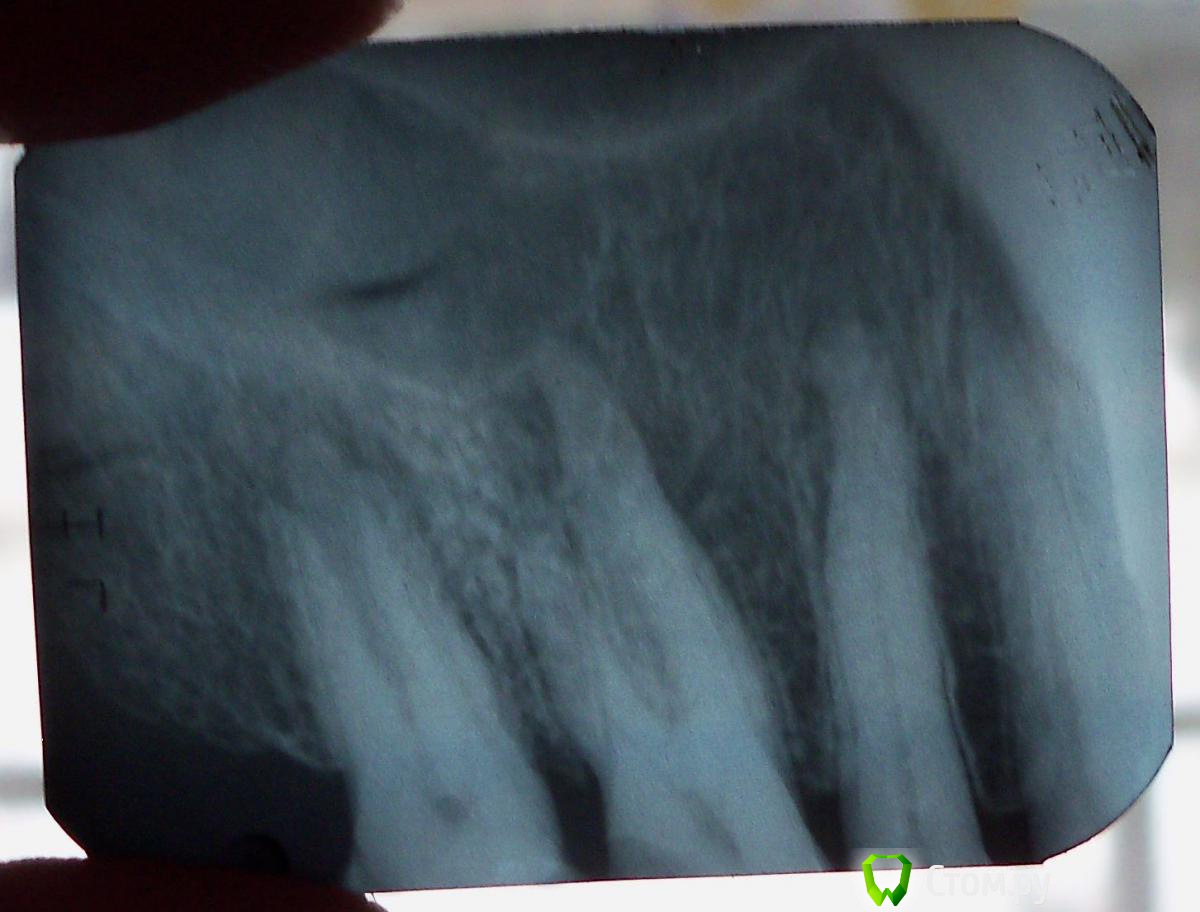

Transiver Опубликовано 13 декабря, 2013 Автор Поделиться Опубликовано 13 декабря, 2013 Выложите панорамный снимок (ОПТГ)Панорамные снимки у нас в поселке не делают. Есть только вот такой. Кстати, по снимку врач сказал, что идет разрушение корней Ссылка на комментарий